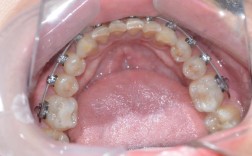

牙齿矫正金属矫正器,作为临床应用最广泛、历史最悠久的正畸装置,通过机械性外力引导牙齿移动至理想位置,是解决各类错颌畸形的重要手段,其核心结构由托槽、弓丝、结扎丝或橡皮圈组成,其中托槽通常由不锈钢或钛合金制成,通过专用粘接剂固定于牙齿唇颊面,...